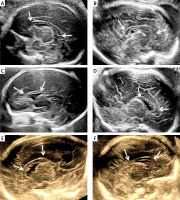

Figure 5

Cases of normal and abnormal CC development. A – Normal; B – the CC is morphologically intact but thinned; C – the CC is shorter and thinner; D – the length of the CC is shorter, but the thickness is thicker; E – the CC is structurally intact, but shortened and thickened; F – although the length of the CC is shorter, the residual part maintains a normal thickness